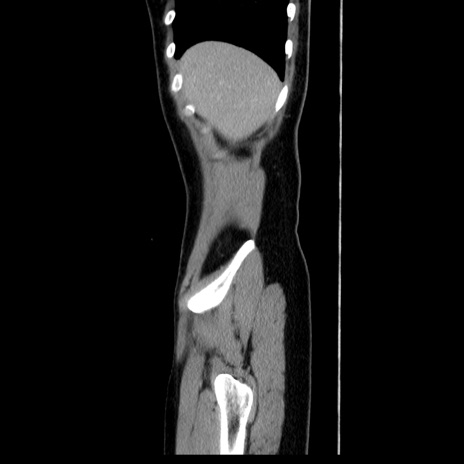

症例39(矢状断像)

【症例】40歳代女性

【主訴】上下腹部痛

【現病歴】2日目から下腹部痛あり。夜間は痛みで眠れなかった。昨日より上腹部痛と下痢が出現。臥位で痛みは軽快したため、休んでいた。本日になって臥位でも立位でも痛みが強くなってきたため救急要請。

【既往歴】子宮内膜症

【身体所見】部:平坦・軟、左上下腹部に圧痛あり、反跳痛あり。

【データ】WBC 21800、CRP 26.78

CT